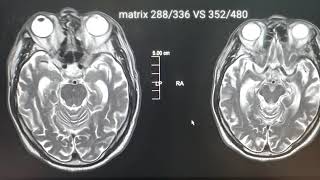

Mri Matrix Sizepixel Image Comparison According...

620

0:56

Radt 110 Ch 29 Matrix & Pixel Size

1.802

5:19